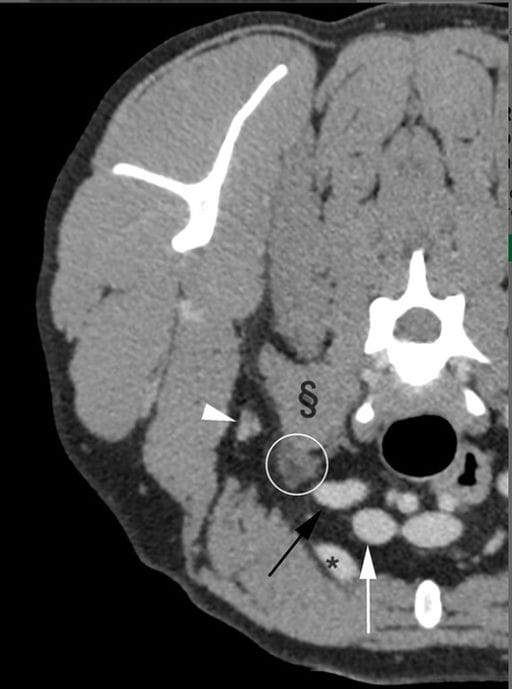

Postcontrast transverse CT image of the cervicothoracic region (level of C6) showing landmarks establishing anatomic location for evaluation. Ventral part of the scalenus muscle (§), axillary vein (black arrow) and artery (white arrow), first rib (*), and axillary lymph node (white arrowhead). The CT images were obtained with a slice thickness of 1 mm, 280 kVp, 200 mA, soft tissue algorithm, viewed with a window width of 400 and a window level of 40. Right is on the left side of the images.